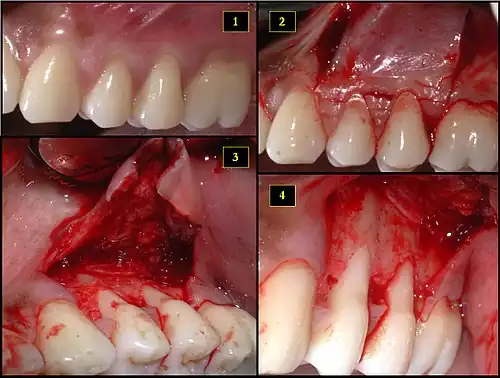

Subepithelial connective tissue graft

- Recipient site exhibits gingival recession on both premolars and first molar (molar recession is not an esthetic issue and will not be treated)

- Incisions prior to flap reflection

- Full thickness flap elevated

- Another viewpoint of the flapped recipient site